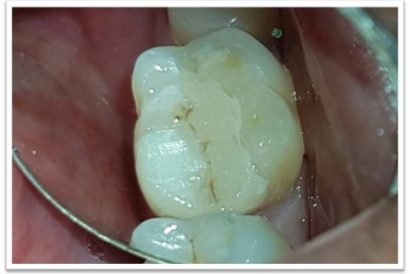

Before

After

Patient Name:Chaitrali Patel

Tooth Involved :46

Diagnosis :Caries Involving Enamel And Dentin Approaching The Pulp : Sympotomatic Reversible Pulpitis

Treatment :Direct Pulp Capping With MTA

Restoration: Direct Composite Restoration Using Nanohybrid Composite